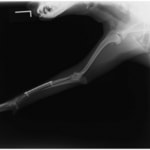

症例3:キルシュナーワイヤーのピンニングによる整復

ペルシャ猫 11ヶ月齢 雄

他院にて左大腿骨遠位の成長板骨折(salter-harrisⅠ型)が認められており、治療相談を目的として来院。当院にて、キルシュナーワイヤーを用いたピンニングにより骨折部位の整復を行いました。術後の経過は良好で、現在も経過観察中です。

術前レントゲン

術後レントゲン

機器

Arthrex社のターゲティングデバイスを用いてピンニングの位置を調整することで、確実な固定を行っています。当院ではこの手術器具以外にも、人の手術にも使用される様々な器具を導入し、手術精度を高め、また医療メーカーと新しい器具の開発、試作にも取り組んでおります。